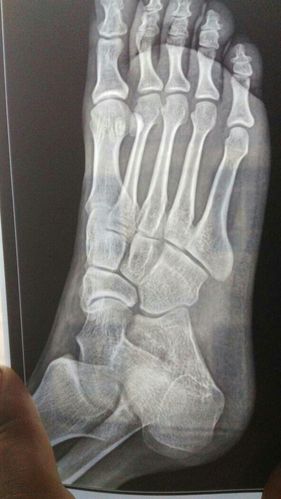

脚骨折片子,骨折片子

跖骨骨折